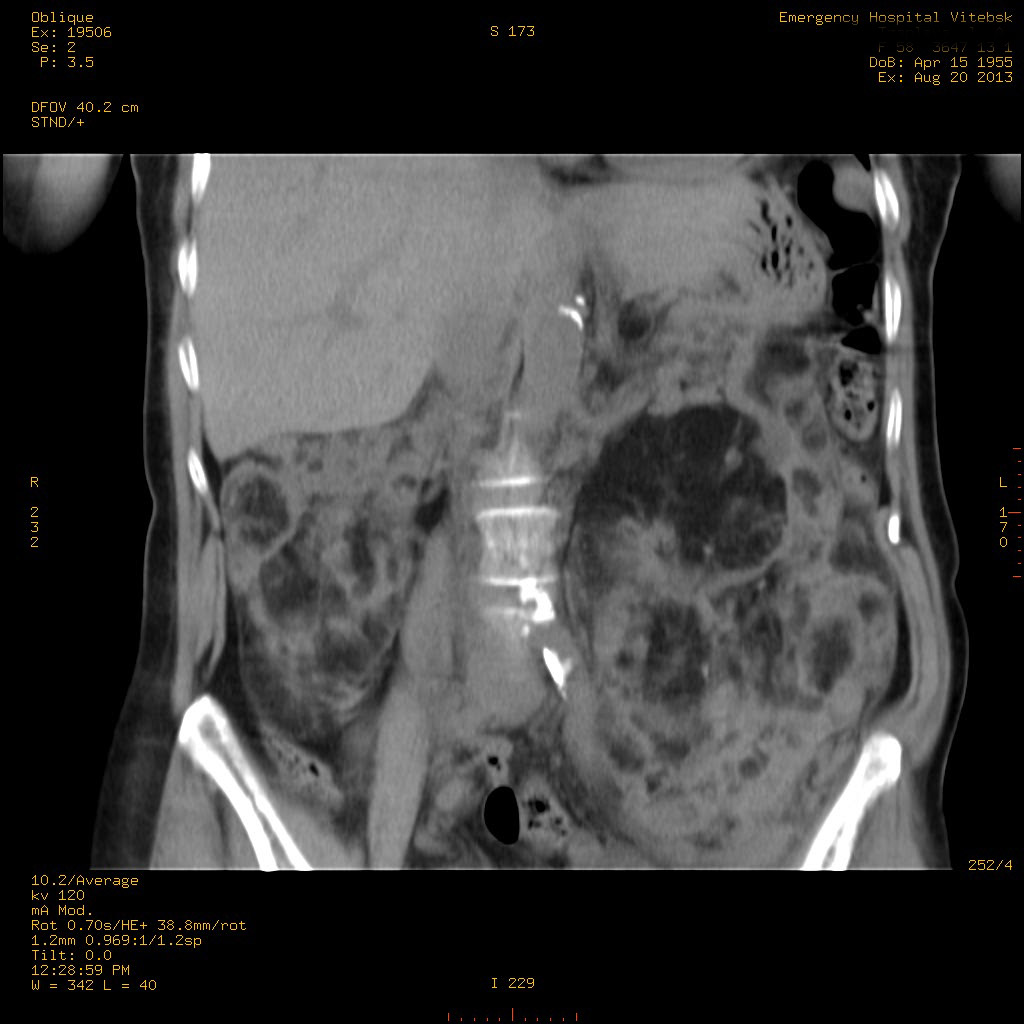

УЗИ почек - туберозный склероз

Пожилая женщина с нормальными мочевиной и креатинином.

Ангиомиолипоматоз почек , думаю компонент туберозного склероза.

Да, туберозный склероз.

Случай консультирован на кафедре радиологии Католического университета г.Лёвен (Бельгия) - зав каф. профессор Р.Оуен.